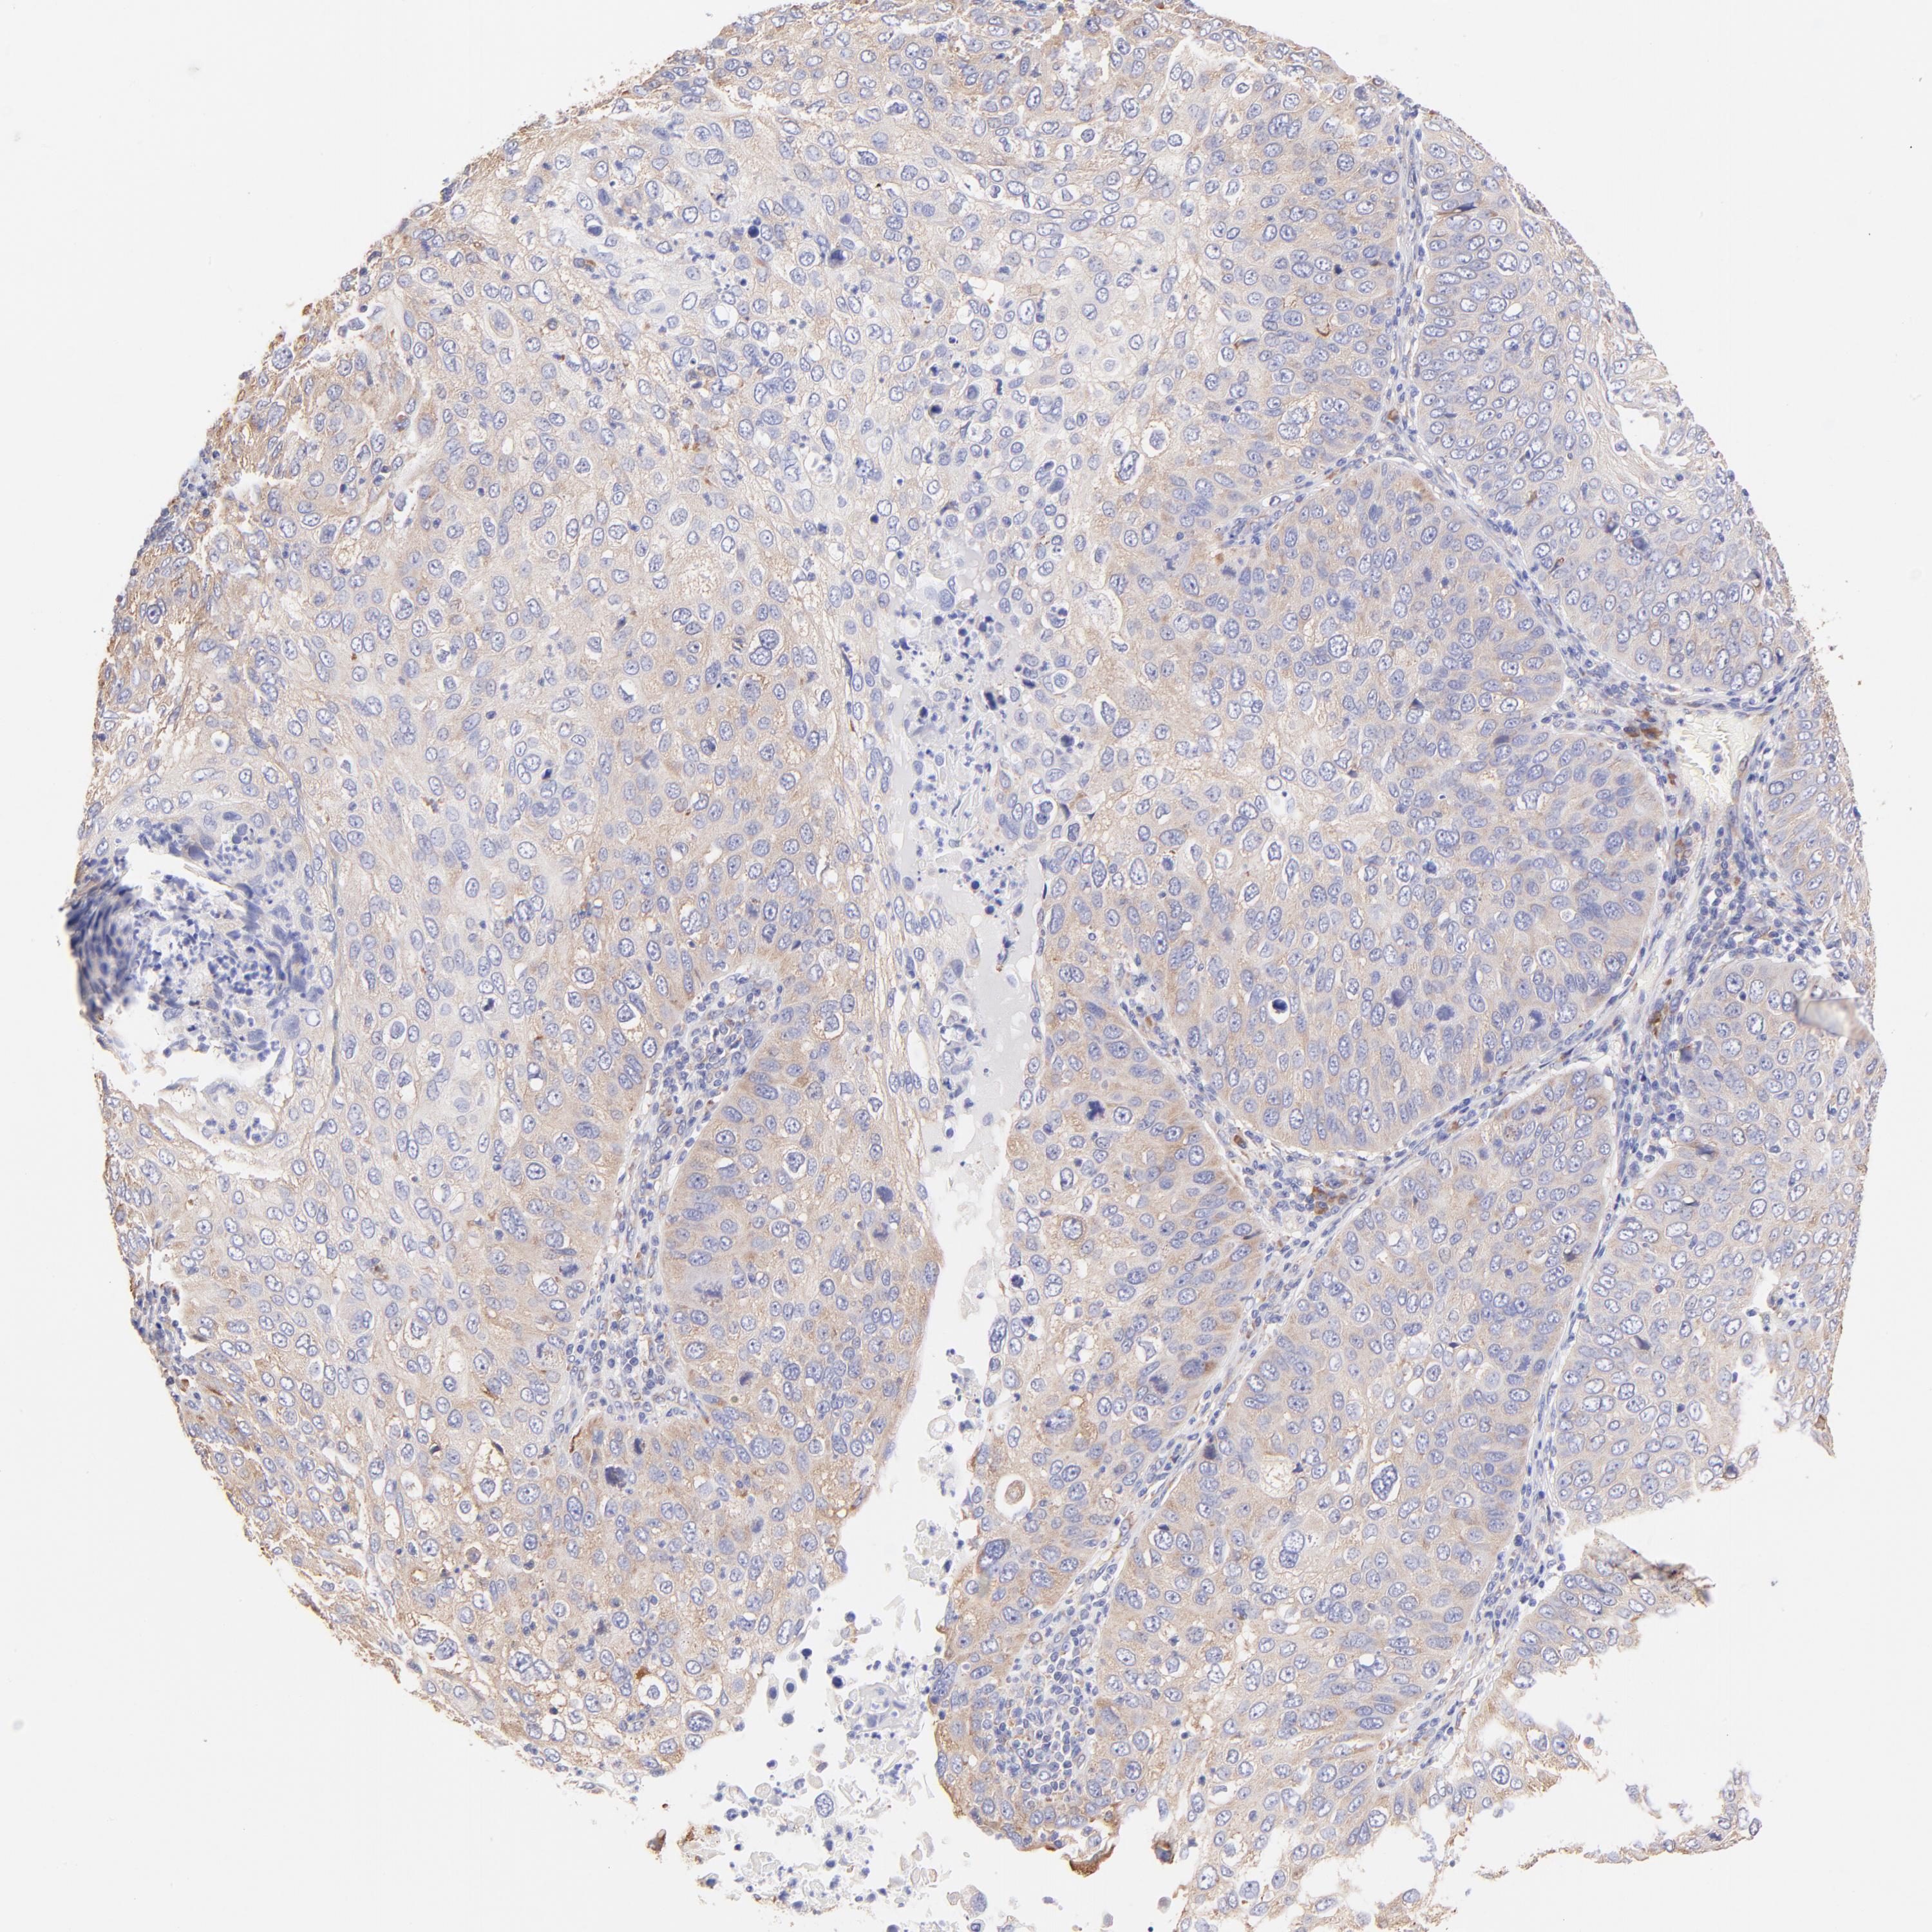

SKIN CANCER - Protein expressioni

A mouse-over function shows sample information and annotation data. Click on an image to view it in a full screen mode. Samples can be filtered based on level of antibody staining by selecting one or several of the following categories: high, medium, low and not detected. The assay and annotation is described here.

Antibody stainingi

Antibody staining in the annotated cell types in the current human tissue is reported as not detected, low, medium, or high, based on conventional immunohistochemistry profiling in selected tissues. This score is based on the combination of the staining intensity and fraction of stained cells.

Each image is clickable and will lead to virtual microscopy that enables deeper exploration of all samples and also displays staining intensity scores, fraction scores and subcellular localization as well as patient and tissue information for each sample.

Antibody HPA002651

Staining

High

Medium

Low

Not detected

Intensity

Strong

Moderate

Weak

Negative

Quantity

>75%

75%-25%

<25%

None

Location

Nuclear

Cytoplasmic/membranous

Cytoplasmic/membranous,nuclear

Squamous cell carcinoma, NOS